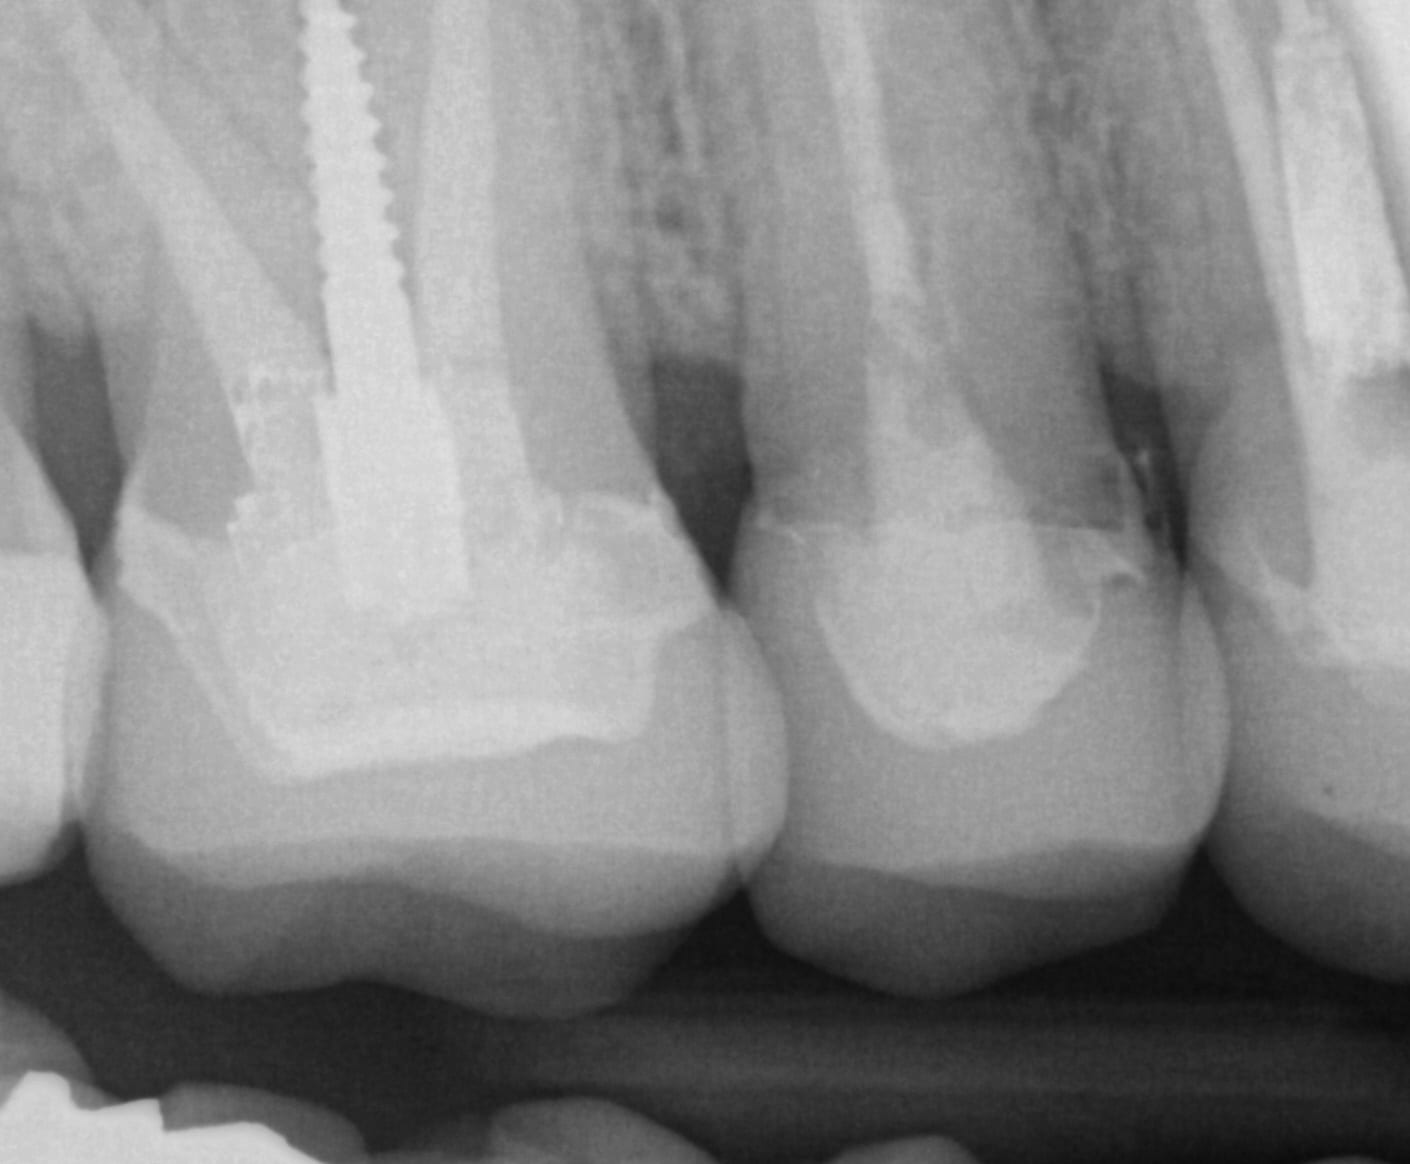

In this clinical presentation, we demonstrate the removal of a crown that has recurrent decay. The bleeding tissue was managed with a double cord technique and expasyl and the margin was captured with the medit i500. The margin was also defined in the native imaging software which allows the user to visualize the detail before designing it or send it off to the lab. Once the case is transferred to cad software, the designed margins carry through and there is an opportunity to modify it